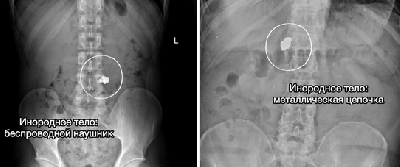

еред вами - подборка самых неожиданных «находок» ушедшего года⠀

Специалисты удаляли беспроводные наушники, украшения и даже гвозди, зажатые в зубах и ненамеренно проглоченные в процессе ремонта.

Случаи курьезные, но проблема крайне серьезная - ежегодно в НИИ поступают десятки пациентов с инородными телами. Им требуется экстренная медицинская помощь и зачастую длительное восстановление.